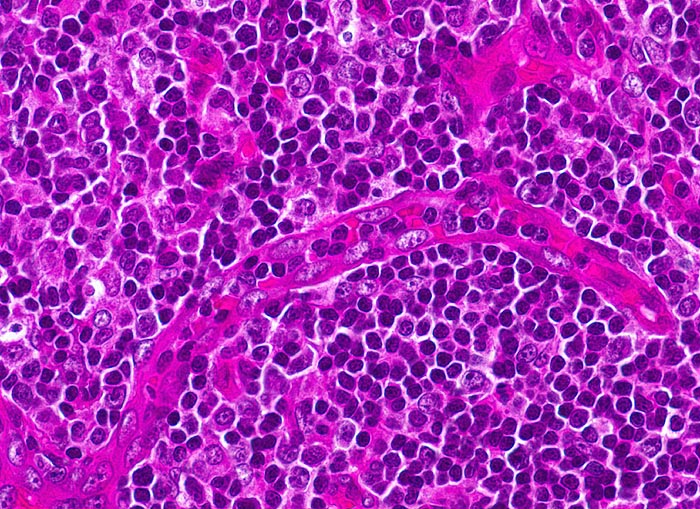

infektiöse Mononukleose

Entzündung infektiös

Tonsille

Lymphatische Gewebe, KM, Milz

Hochendotheliale postkapilläre Venole mit gesteigerter Lymphozyten-Rezirkulation. Daneben buntes Zellbild: kleine Lymphozyten, stimulierte Lymphozyten, Immunoblasten mit zentralem Nukleolus und Plasmazellen mit paranukleärer Aufhellung des Zytoplasmas.

Tonsillektomie bei einem Studenten mit Angina, Lymphknotenschwellungen und einer Lymphozytose im Blut.

Histologie

400